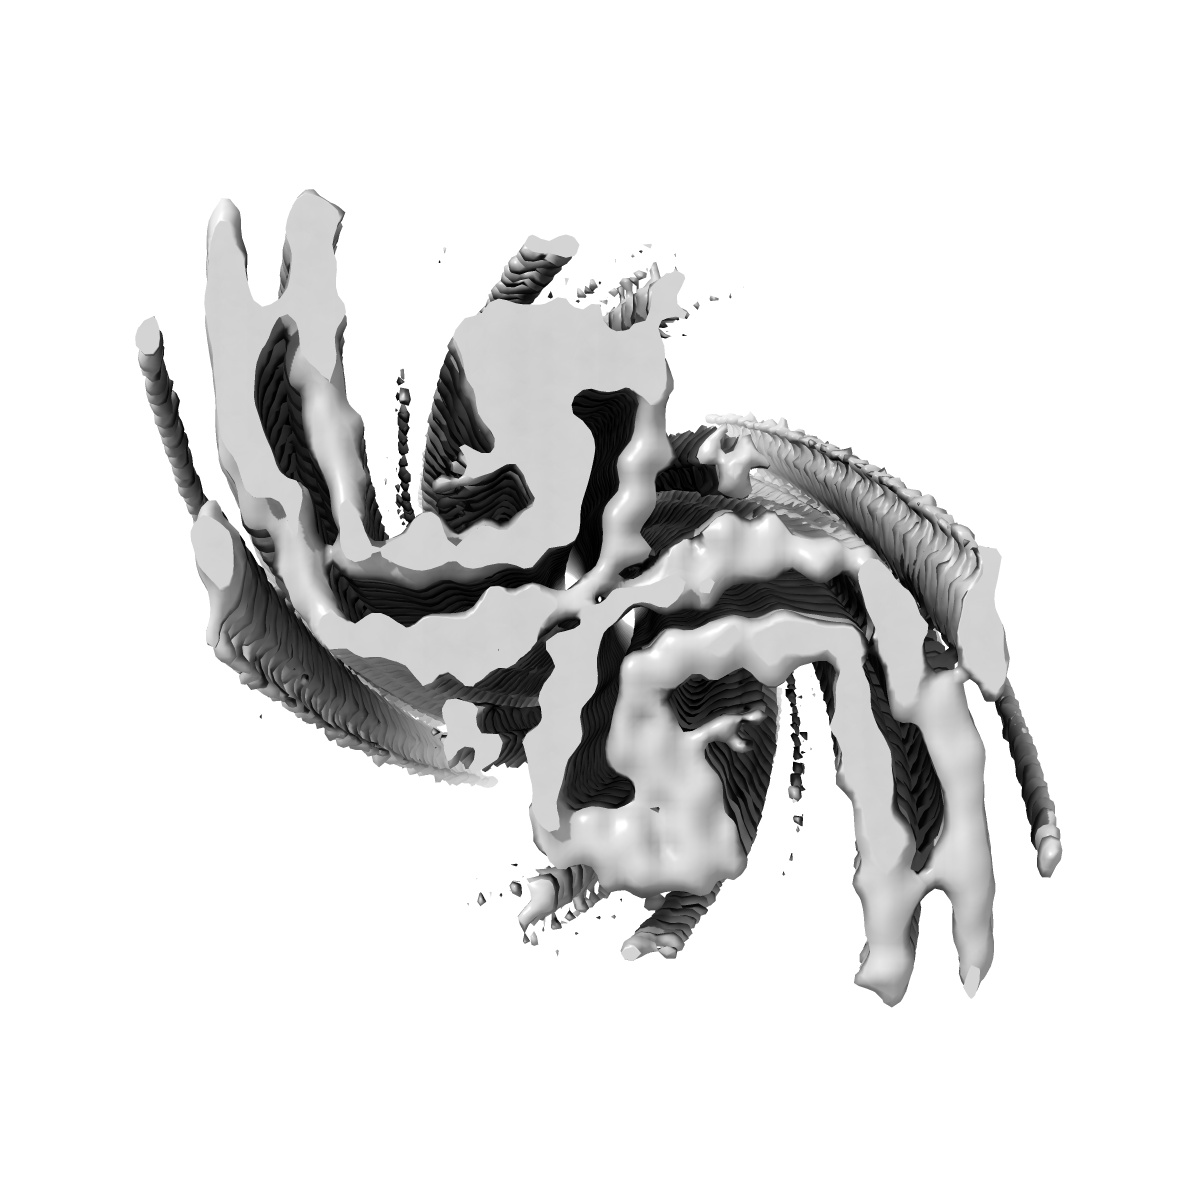

Tau Paired Helical Filament from Alzheimer's Disease incubated with EGCG for 3 hours

Helical reconstruction3.8 Å

Sample: Tau Paired Helical Filament from Alzheimer's Disease incubated with EGCG for 3 hours